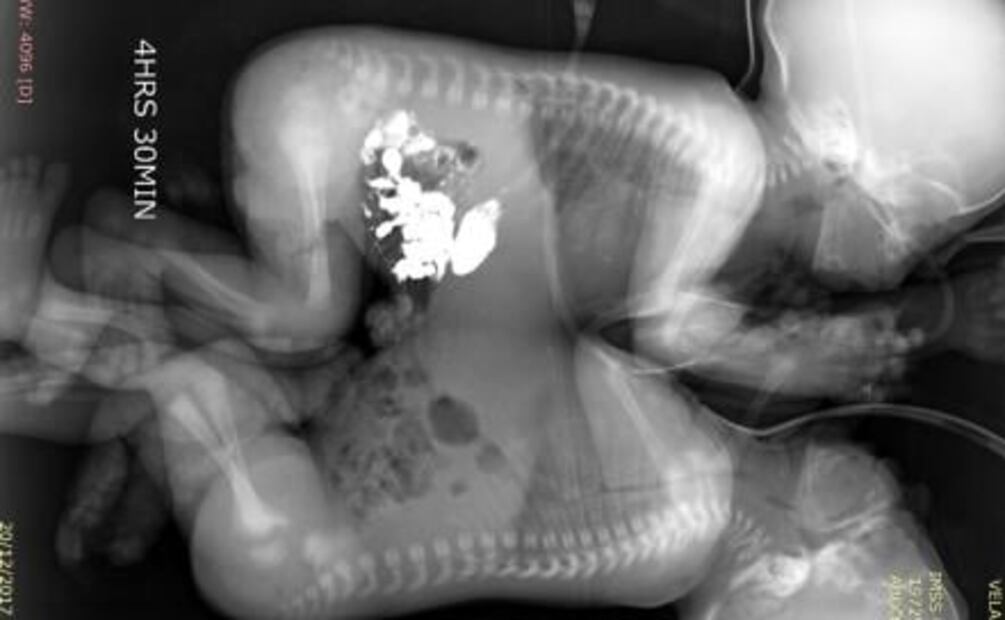

Son gemelos , pero compartían más que rasgos físicos, estaban unidos por el tórax y el abdomen , al cumplir 41 días de nacidos, especialistas del Instituto Mexicano del Seguro Social ( IMSS ) en León, Guanajuato, separaron con éxito a los siameses.

Después del alumbramiento, los menores de edad fueron sometidos a exámenes de tomografía, ecocardiograma y resonancia magnética, cuando cumplieron 41 días de vida, se decidió programar la cirugía que los separaría.

La intervención quirúrgica se realizó por un equipo multidisciplinario de cirujanos, anestesistas y grupo de enfermería , comenzó a las 9:00 horas; de manera cuidadosa ejecutaron la incisión en la línea media que unía a los gemelos y mediante la técnica de electrocoagulación , lograron separarlos a las 12:43 horas, sin que se presentaran complicaciones.